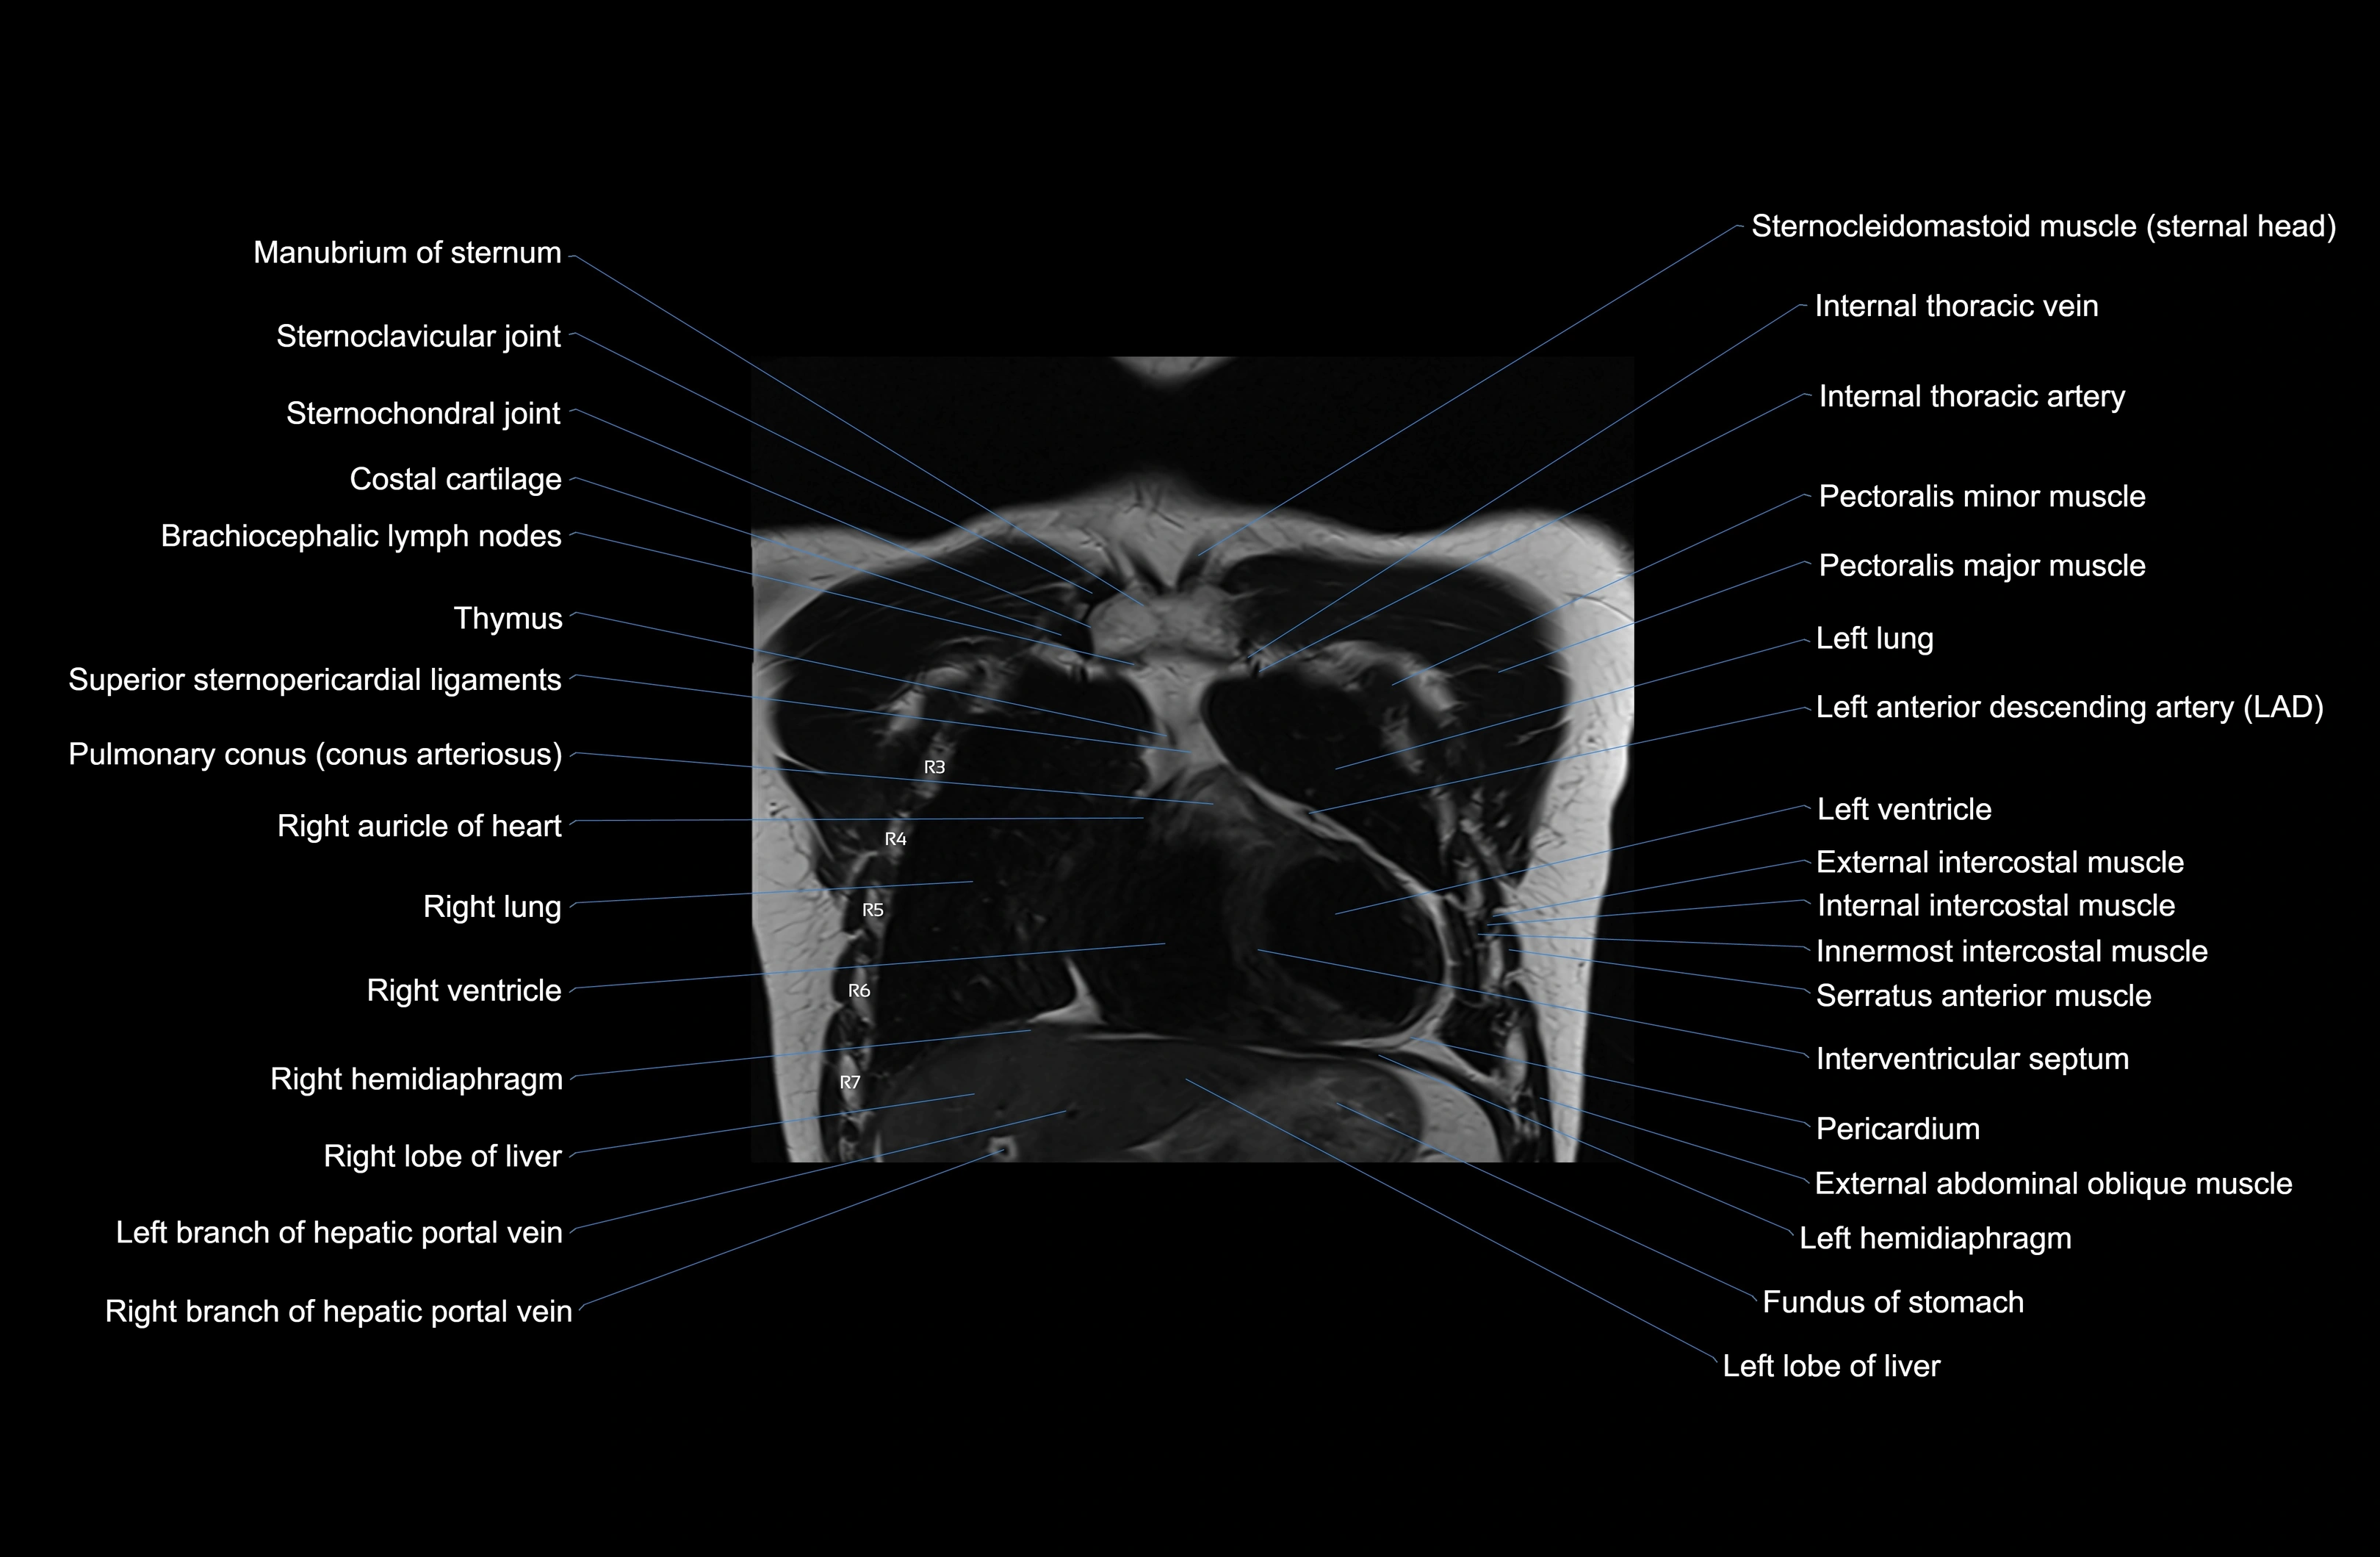

- T (Thoracic spine)